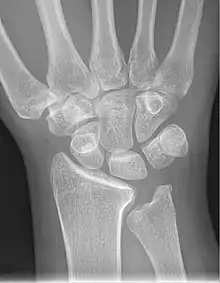

- Left hand x-ray with Kienbock's Disease showing 4 mm negative ulnar variance and Kienbock's Disease Stage IIIB

- X-ray showing stage IIIB on right wrist, with ulnar impingement.